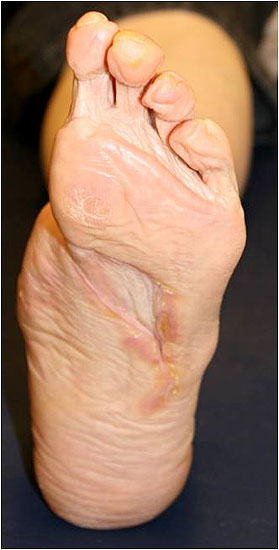

4. Weichteile und Malum perforans

Die Verminderung der Durchblutung und die periphere und autonome Neuropathie führen zur Atrophie der Weichteile. Die wird Haut dünn, spröde und brüchig, es kommt zu einer Atrophie der plantaren Fettschicht und der plantaren Fußmuskeln. Nur das Fußskelett behält seine Form, sofern keine Osteoarthropathie vorliegt. Durch den Verlust der Weichteile kommt der Knochen auf der papierdünnen Haut zu liegen. Durch Scherkräfte, die nun nicht mehr durch den Weichteilmantel abgefangen werden können, entstehen Schwielen und Weichteilnekrosen. Die bakterielle Besiedelung der Schwielen und die brüchige Haut in Verbindung mit der schlechten Durchblutungssituation liefern die Grundlage für die Entstehung eines lokalen Weichteilinfektes 21. Durch Ausweitung des Infektes in die Tiefe entsteht ein Malum perforans bis hin zur Osteomyelitis. Ist der Knochen infiziert, ist eine dauerhafte Sanierung des Ulkus nur durch die Entfernung des betroffenen Knochens zu erreichen 22. Um solch eine Entwicklung zu verhindern, kann nicht eindringlich genug auf die prophylaktischen Maßnahmen verwiesen werden.